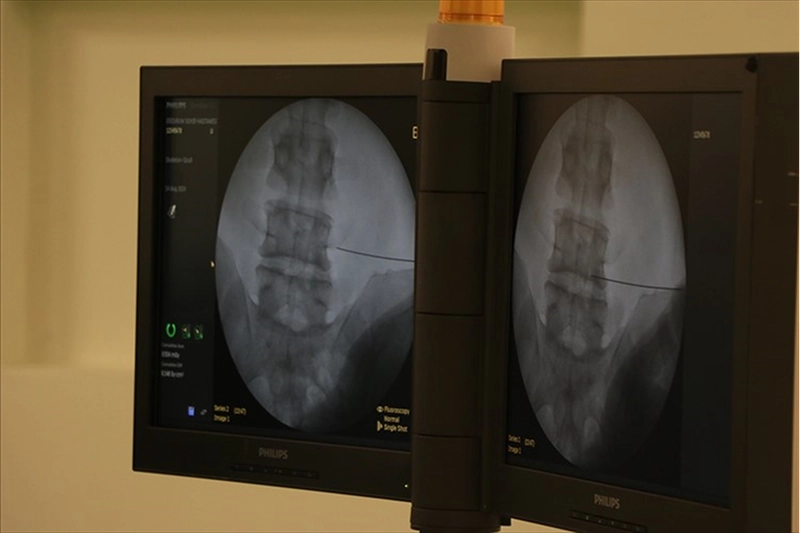

"Cerrahi yöntem hastaya özel olarak planlanıyor"Fıtıkların zamanla büyüme eğiliminde olduğuna işaret eden Dr. Öğretim Üyesi Uluşahin, tedavi edilmeyen vakalarda organ sıkışması, bağırsak tıkanması ve hayati risk taşıyan boğulmuş fıtık gelişebileceğine dikkati çekti.

"Günümüzde fıtık ameliyatlarının açık ve laparoskopik (kapalı) yöntemlerle başarıyla uygulanıyor. Cerrahi yöntem hastaya özel olarak planlanıyor. Günümüzde fıtık ameliyatları son derece güvenlidir. Buna karşın fıtıkla uzun süre yaşamak ciddi riskler barındırır. Doğru bilgi, doğru zaman ve doğru tedavi hayat kurtarır."